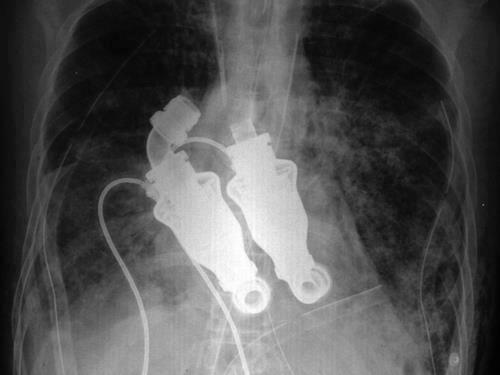

The turbine-like device, that are simple whirling rotors, developed by the doctors does not beat like a heart, rather provides a ‘continuous flow’ like a garden hose.Craig Lewis was a 55-year-old, dying from amyloidosis, which causes a buildup of abnormal proteins. The proteins clog the organs so much that they stop working, according to NPR.

But after the operation, with the ‘machine’ as his heart’s replacement, Lewis’ blood continued to spin and move through his body.However, when doctors put a stethoscope to his chest, no heartbeat or pulse can be heard (only a ‘humming’ sound)—which “by all criteria that we conventionally use to analyze patients”, Doctor Cohn said, he is dead.

Drs Billy Cohn, left, and Bud Frazier, right, invented the ‘continuous flow’ device and successfully installed it in Mr Lewis.